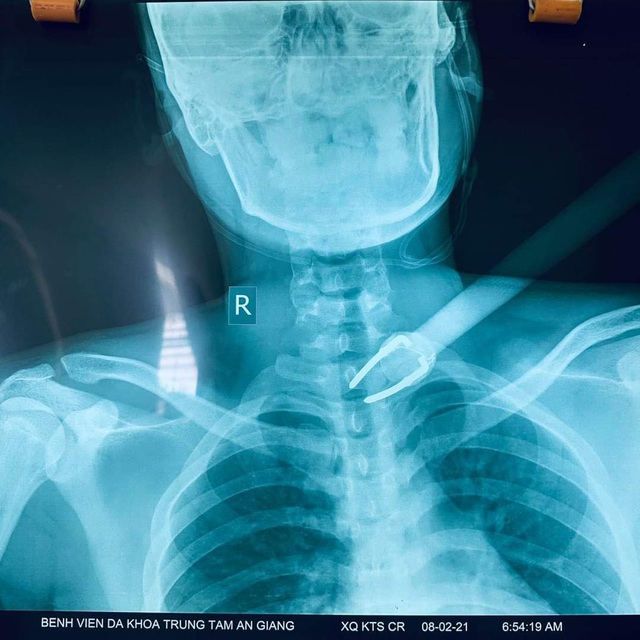

Hình ảnh bệnh nhân D. khi chuyển tới bệnh viện với cây tên (cây chĩa) còn xuyên cổ

Hình ảnh chụp X- quang của bệnh nhân D.

Mũi tên lạ được lấy ra từ cổ của bệnh nhân có chiều dài khoảng 50cm với phần mũi kim loại chia làm 2 nhánh như mũi chĩa dài 8cm với đường kính 2mm.

Theo ghi nhận của các bác sĩ, mũi tên đâm xuyên vùng cổ bệnh nhân chạm đến tận đốt sống cổ C7-D1. Rất may mắn là mũi tên chỉ gây bóc tách cơ vùng cổ - ngực, không gây thủng hay tổn thương mạch máu - thần kinh - khí quản - thực quản. Điều này góp phần giúp các bác sĩ giữ lại mạng sống của bệnh nhân bởi chỉ cần tổn thương một trong 4 mạch máu trên thì bệnh nhân có thể tử vong ngay lập tức hoặc tối thiểu cũng có thể gây di chứng tàn phế nặng nề về sau. Hiện bệnh nhân đã tỉnh táo, giao tiếp tốt, không còn đau vùng vết thương ở cổ.